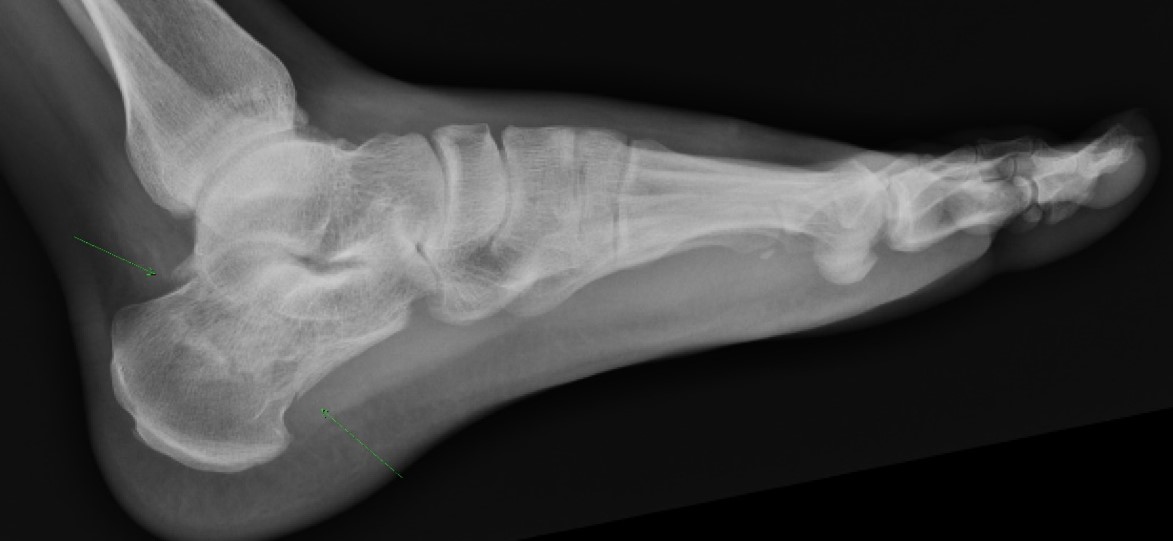

Normal Bohler's angle (star) and trabeculations in a patient with no calcaneus injury. Bohler's angle is formed by intersecting two lines. One is drawn from the most cephalic portion of the tuberosity (red dot) to the highest point of the posterior facet (white dot). The other line is drawn from the highest point of the posterior facet (white dot) to the most cephalic part of the anterior process (blue dot).